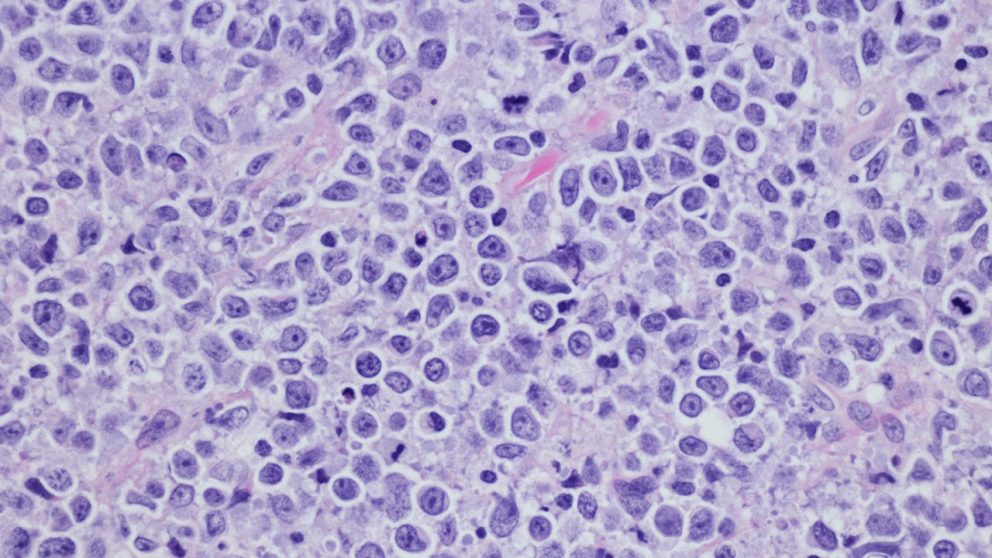

In the study, published today in Cancer Cell, researchers profiled samples from 232 patients with LBCL to create "LymphoMAPs" that provide detailed information about the environment surrounding lymphoma cells and how they relate to clinical data and patient outcomes. The findings offer new insights to guide physicians toward the best potential clinical pathways for patients based on the underlying biology of the tumors profiled.

In this study, researchers profiled single cells from 232 biopsy samples from 217 newly diagnosed and previously treated lymphoma patients. In total, researchers profiled over 1.8 million cells, which is approximately 10 times more than the previous largest study of lymphoma.